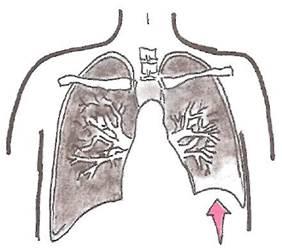

Следует также иметь в виду, что при формировании обтурационного ателектаза возможно снижение впутриплеврального давления, что также способствует усилению секреции жидкости париетальной плеврой (рис. 7).

Рис. 7.

Один из механизмов образования плеврального выпота при обтурационном ателектазе